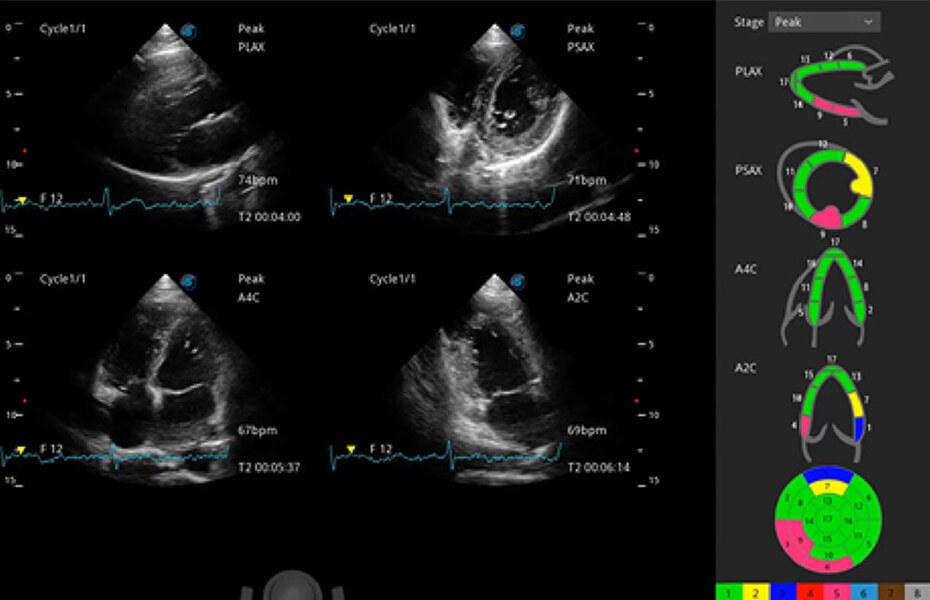

ProPet 60 作為一款高端臺式動物超聲設備,為動物醫(yī)生的日常診斷提供了一系列貼合動物臨床需求、解決臨床實際問題的高級成像功能。憑借全系列高清探頭,滿足醫(yī)生對腹部、心臟、生殖、淺表、肌骨等成像的所有需求,切實幫助您提升檢查效率,提高診斷信心。